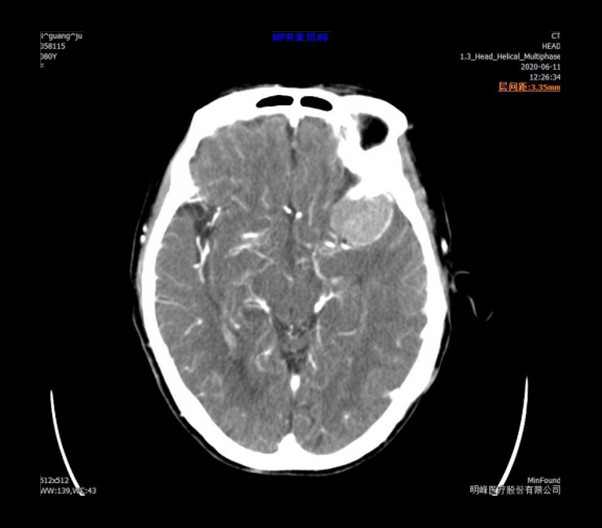

臨床畫廊